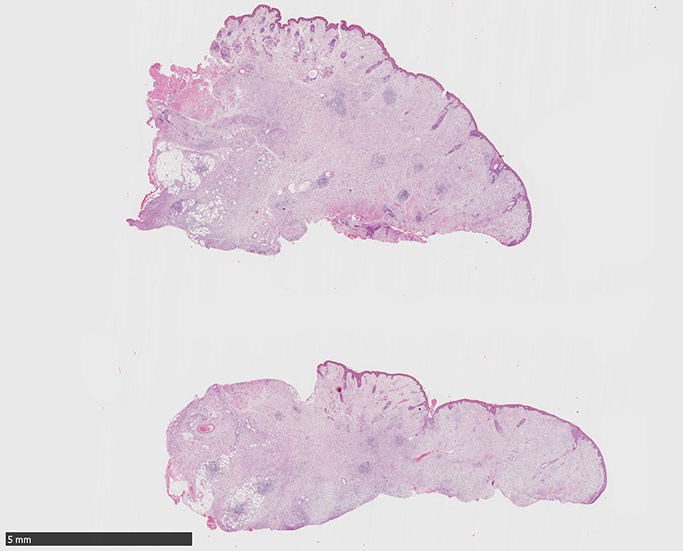

SPS244-Case01 右下眼瞼腫瘤 70歳代女性

初回皮膚生検組織

SPS244-Case02 項部皮下腫瘤 70歳代女性

潰瘍びらんはない割面loupe像